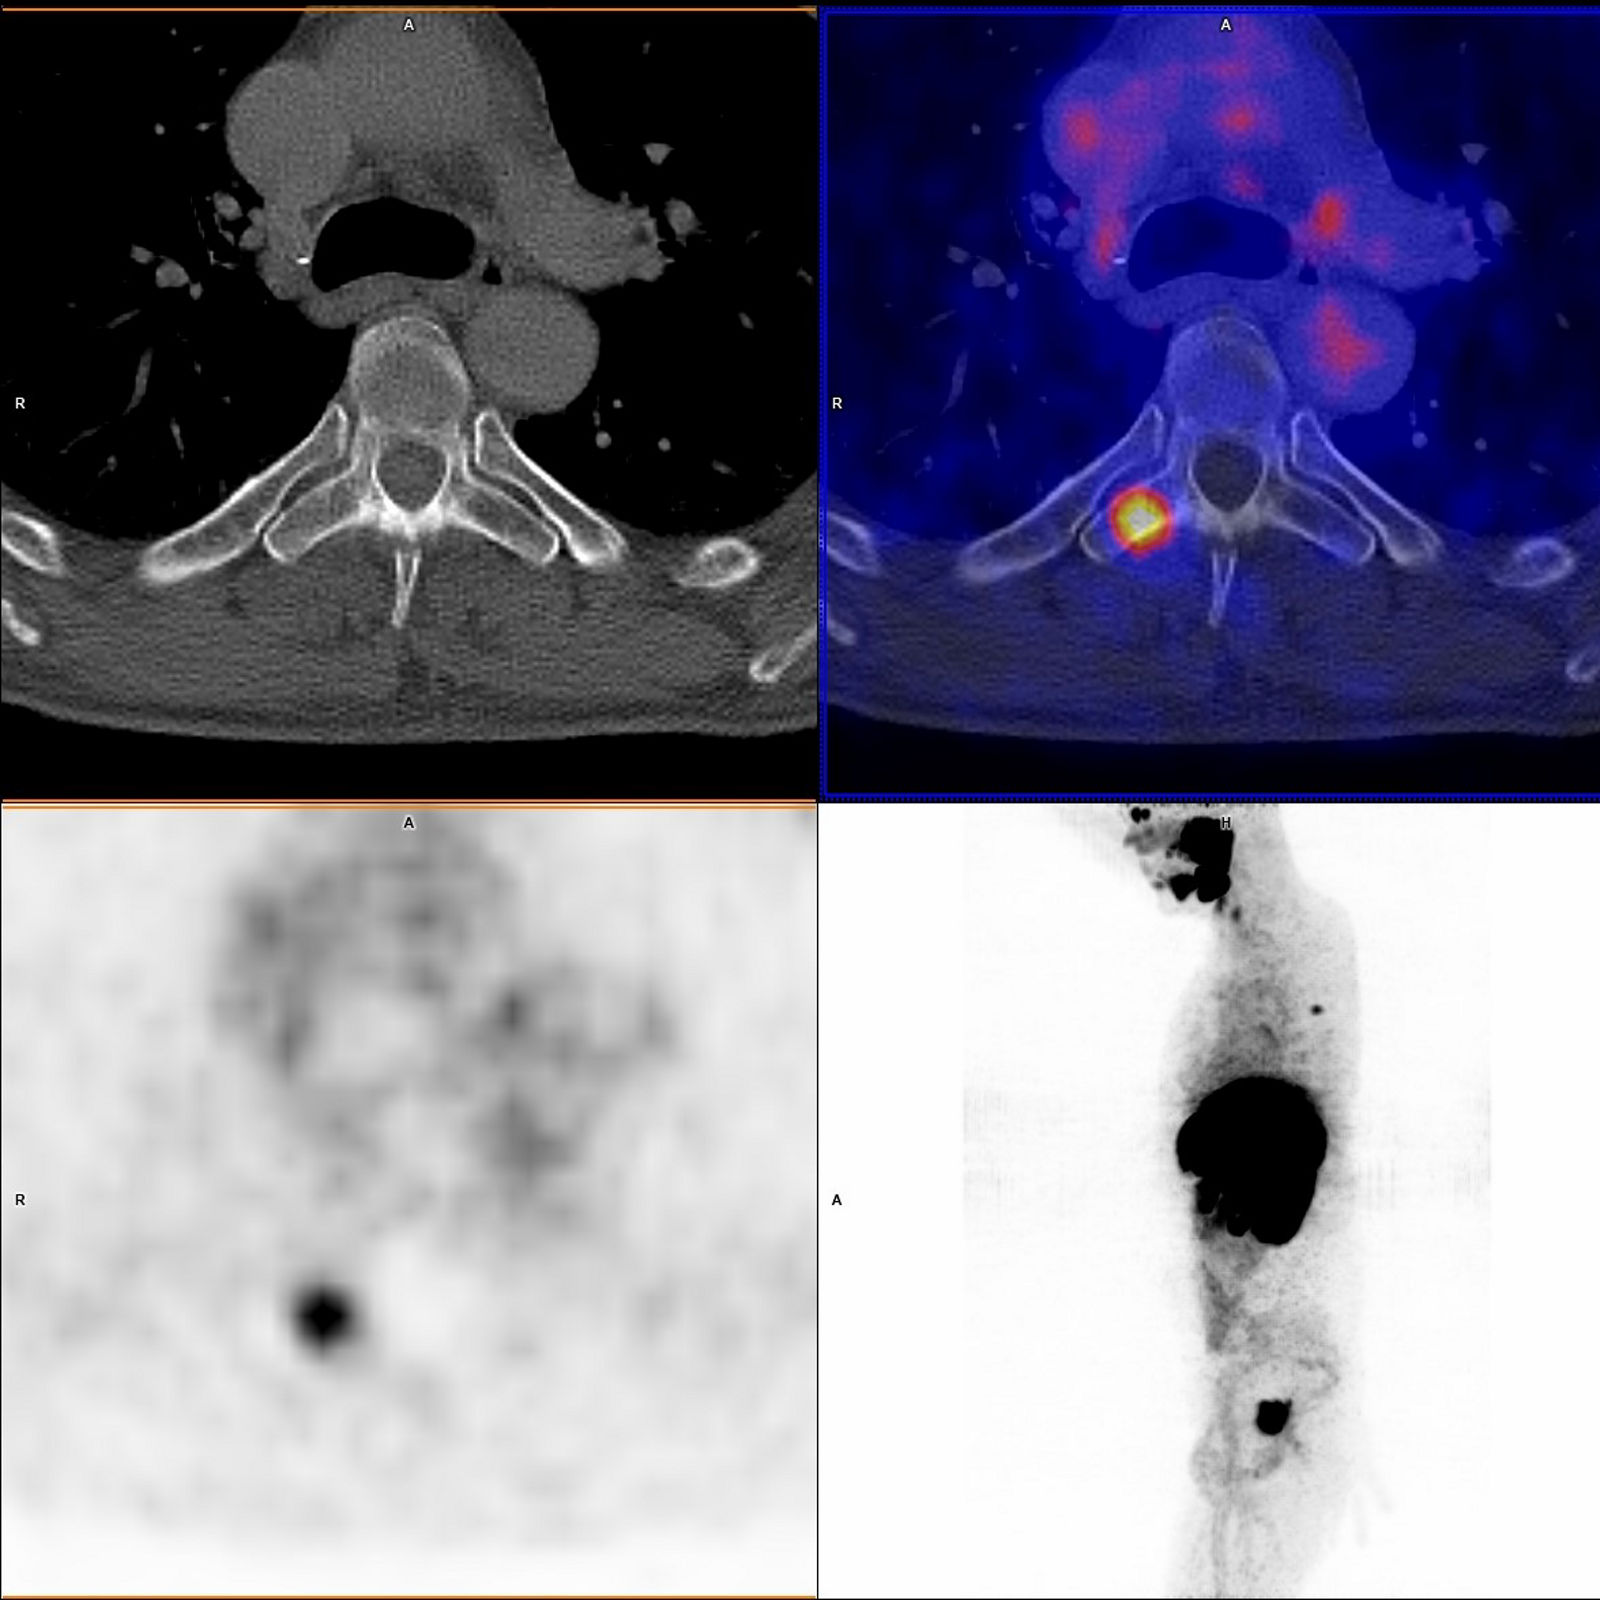

Dieses Kombinationsgerät, bestehend aus einer Einheit für Positronen-Emission-Tomographie (PET) und einer für Computertomographie (CT), ermöglicht die zeitgleiche Darstellung der Stoffwechselaktivitäten und der Anatomie eines Patienten.

Die PET stellt durch den Einsatz schwach radioaktiver Substanzen unterschiedliche Stoffwechselvorgänge dar, die durch die Kombination mit der CT dann genau anatomisch zugeordnet werden können. Dadurch wird insbesondere in der Onkologie eine präzise und rasche Lokalisation von Tumorgewebe (Primärtumoren oder auch Metastasen) möglich und eine Therapie kann gezielter geplant werden. Manche Therapie wird durch die PET-CT in eine andere Richtung gelenkt, unnötige Therapien werden vermieden.